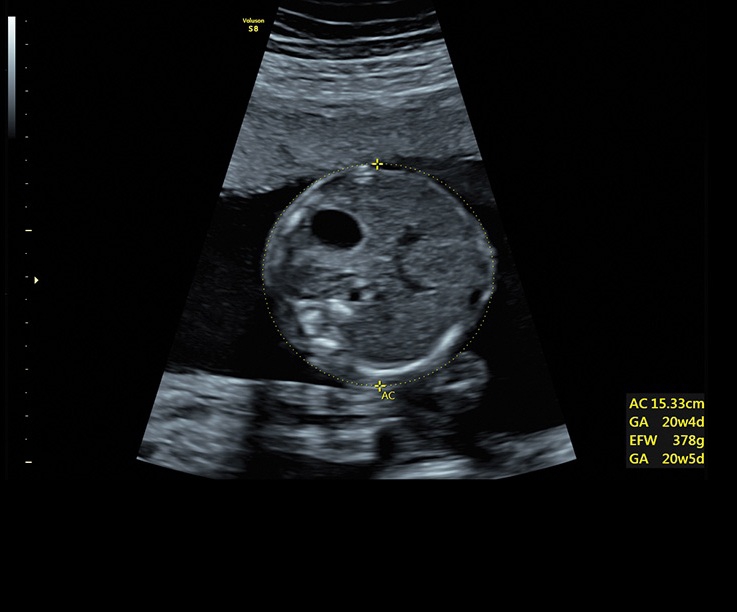

Ультразвуковая платформа Voluson S8 представляет собой оборудование экспертного класса с передовыми возможностями и высоким уровнем автоматизации процессов. Она позволяет проводить сканирование в режимах 2D, 3D и 4D с высоким качеством изображений.

Аппарат Voluson S8 базируется на надежной платформе VCA, которая имеет множество положительных отзывов. Она обладает высококонтрастной технологией объемной реконструкции, обеспечивая качественное воспроизведение изображений. Информация выводится на широкоформатный цветной монитор размером 23 дюйма для убедительной демонстрации плода будущим родителям и облегчения работы врача.

• Технология автоматической фетометрии в 2D режиме (SonoBiometry): Эта технология позволяет автоматически измерять бипариетальный размер, окружность головы, окружность живота, длину бедра и плеча плода, обеспечивая точные и надежные измерения.

• Высокое качество изображений: Voluson S8 обеспечивает высококачественные изображения, позволяющие детально оценить состояние плода и обнаружить возможные патологии.